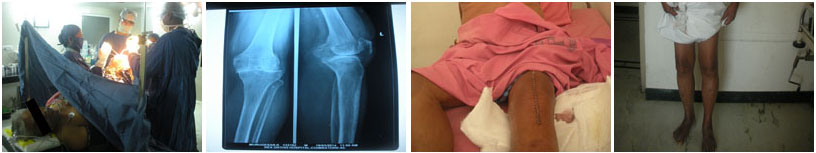

Primary total knee replacement helps relieve severe knee pain and stiffness caused by arthritis or long-term joint damage. The procedure restores smooth movement and allows patients to resume daily activities with improved comfort.

From diagnosis to surgery and recovery, our team ensures you receive expert treatment and individual attention throughout your treatment journey